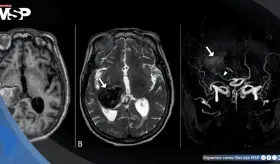

Las imágenes sugirieron un tumor con hueso, grasa y tejido cerebral dentro del recto, confirmando un diagnóstico poco común que solo se documenta en uno de cada 35.000 a 40.000 casos a nivel mundial.